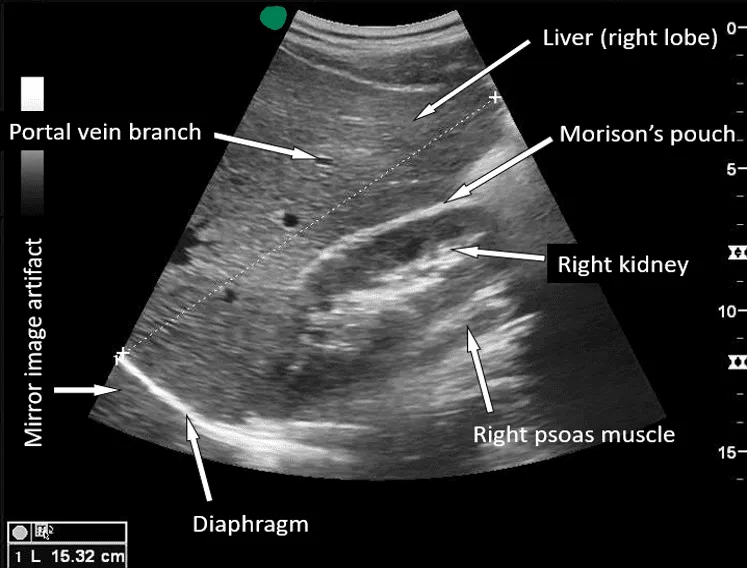

- Positive FAST exam (1 pt)